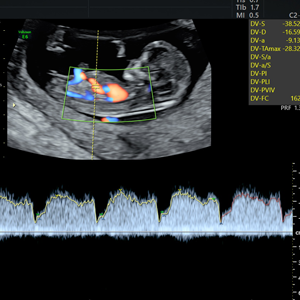

Dr. Homero Flores Tamez

Ginecología y Obstetricia

Medicina Materno Fetal

- Instituto Nacional de Perinatología

- Pionero en México en ofrecer diagnóstico por ultrasonido dentro del consultorio, así como en incorporar tecnología 3D y Doppler.